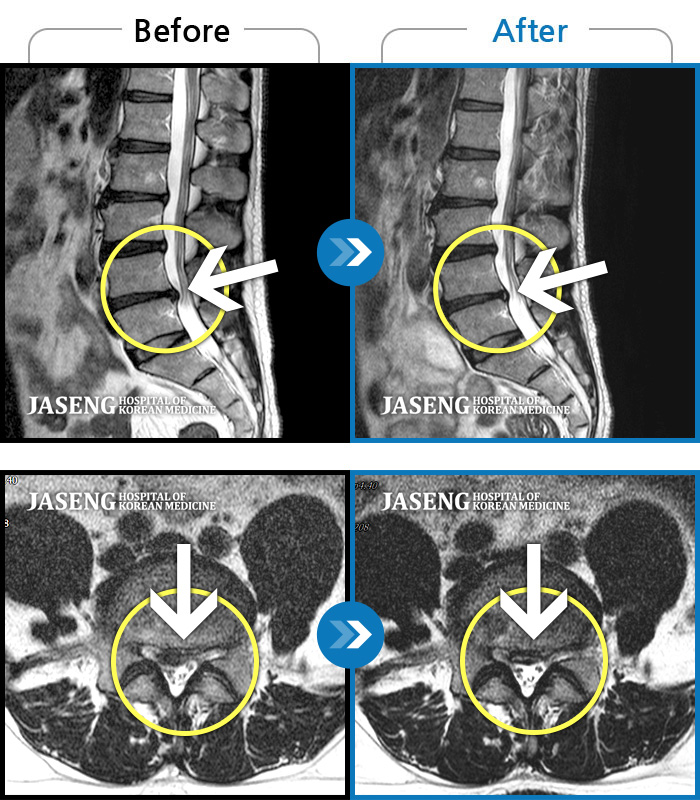

MRI 치료사례

우측 허리 통증 및 다리 저림이 심하여 앉거나 바로 눕는 것도 힘든 상태로 내원하셨습니다. 감각 저하도 동반되어 심각한 신경손상이 의심되는 상황이었습니다.